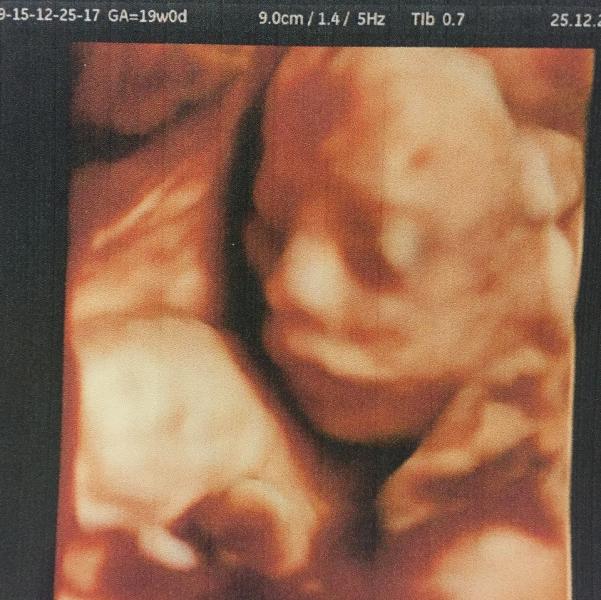

Была на плановом узи у Плотко. Хороший такой дядька!!! Каждое своё движение комментировал. Все подробно рассказывал, что да как у малыша. Срок ставят 19-20 недель. Развивается в соответствии со сроком. Компьютерный вес плода 321 гр. (вот какие мы большие🤗🤗🤗). Слава богу 🙏🙏 патологий нет. У нас будет ещё один сыночек 😊😊😊. Видимо не дано мне воспитывать девчонок 😜. А я и рада, что снова мальчик и сыночек рад братику 😋😋😋. Буду продолжать молится богу о его здоровье. Люблю ❤️ тебя мой маленький...